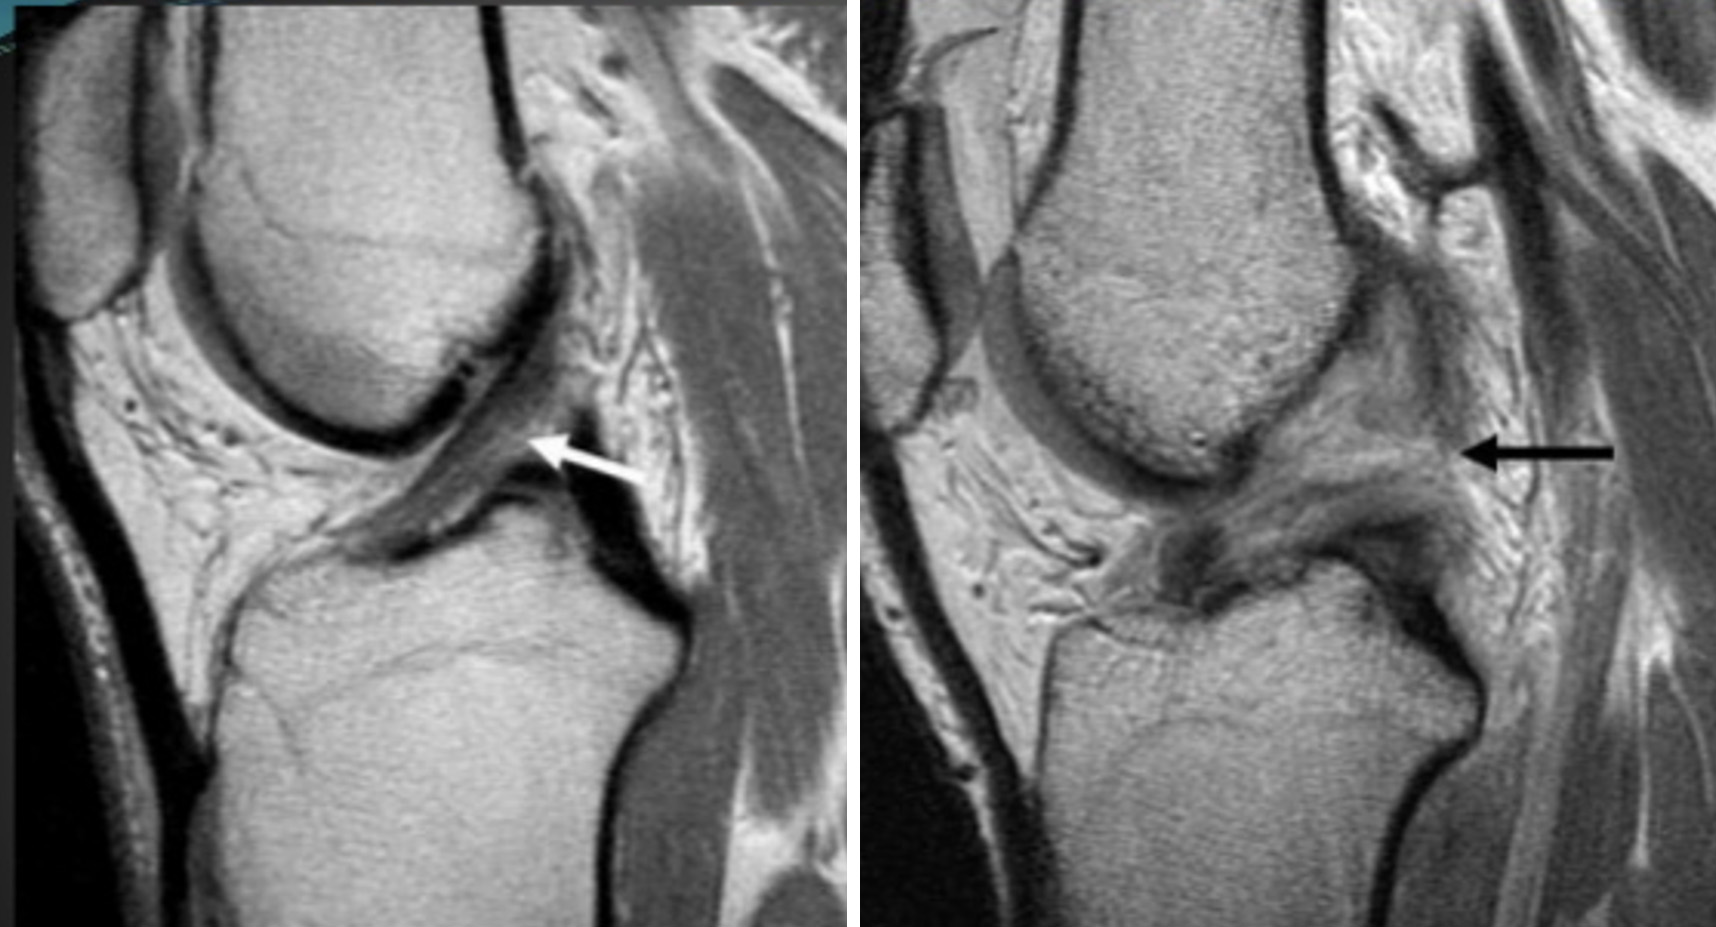

A Ressonância Magnética é o exame de escolha em contexto de suspeita de lesão do LCA, permitindo avaliar igualmente outras lesões associadas – ligamentares, meniscais ou condrais – Figura 7.

Imagem de ressonância magnética. Seta à esquerda com LCA intacto. Imagem à direita com rotura do LCA.

Figura 7 – Imagem de ressonância magnética. Seta à esquerda com LCA intacto. Imagem à direita com rotura do LCA